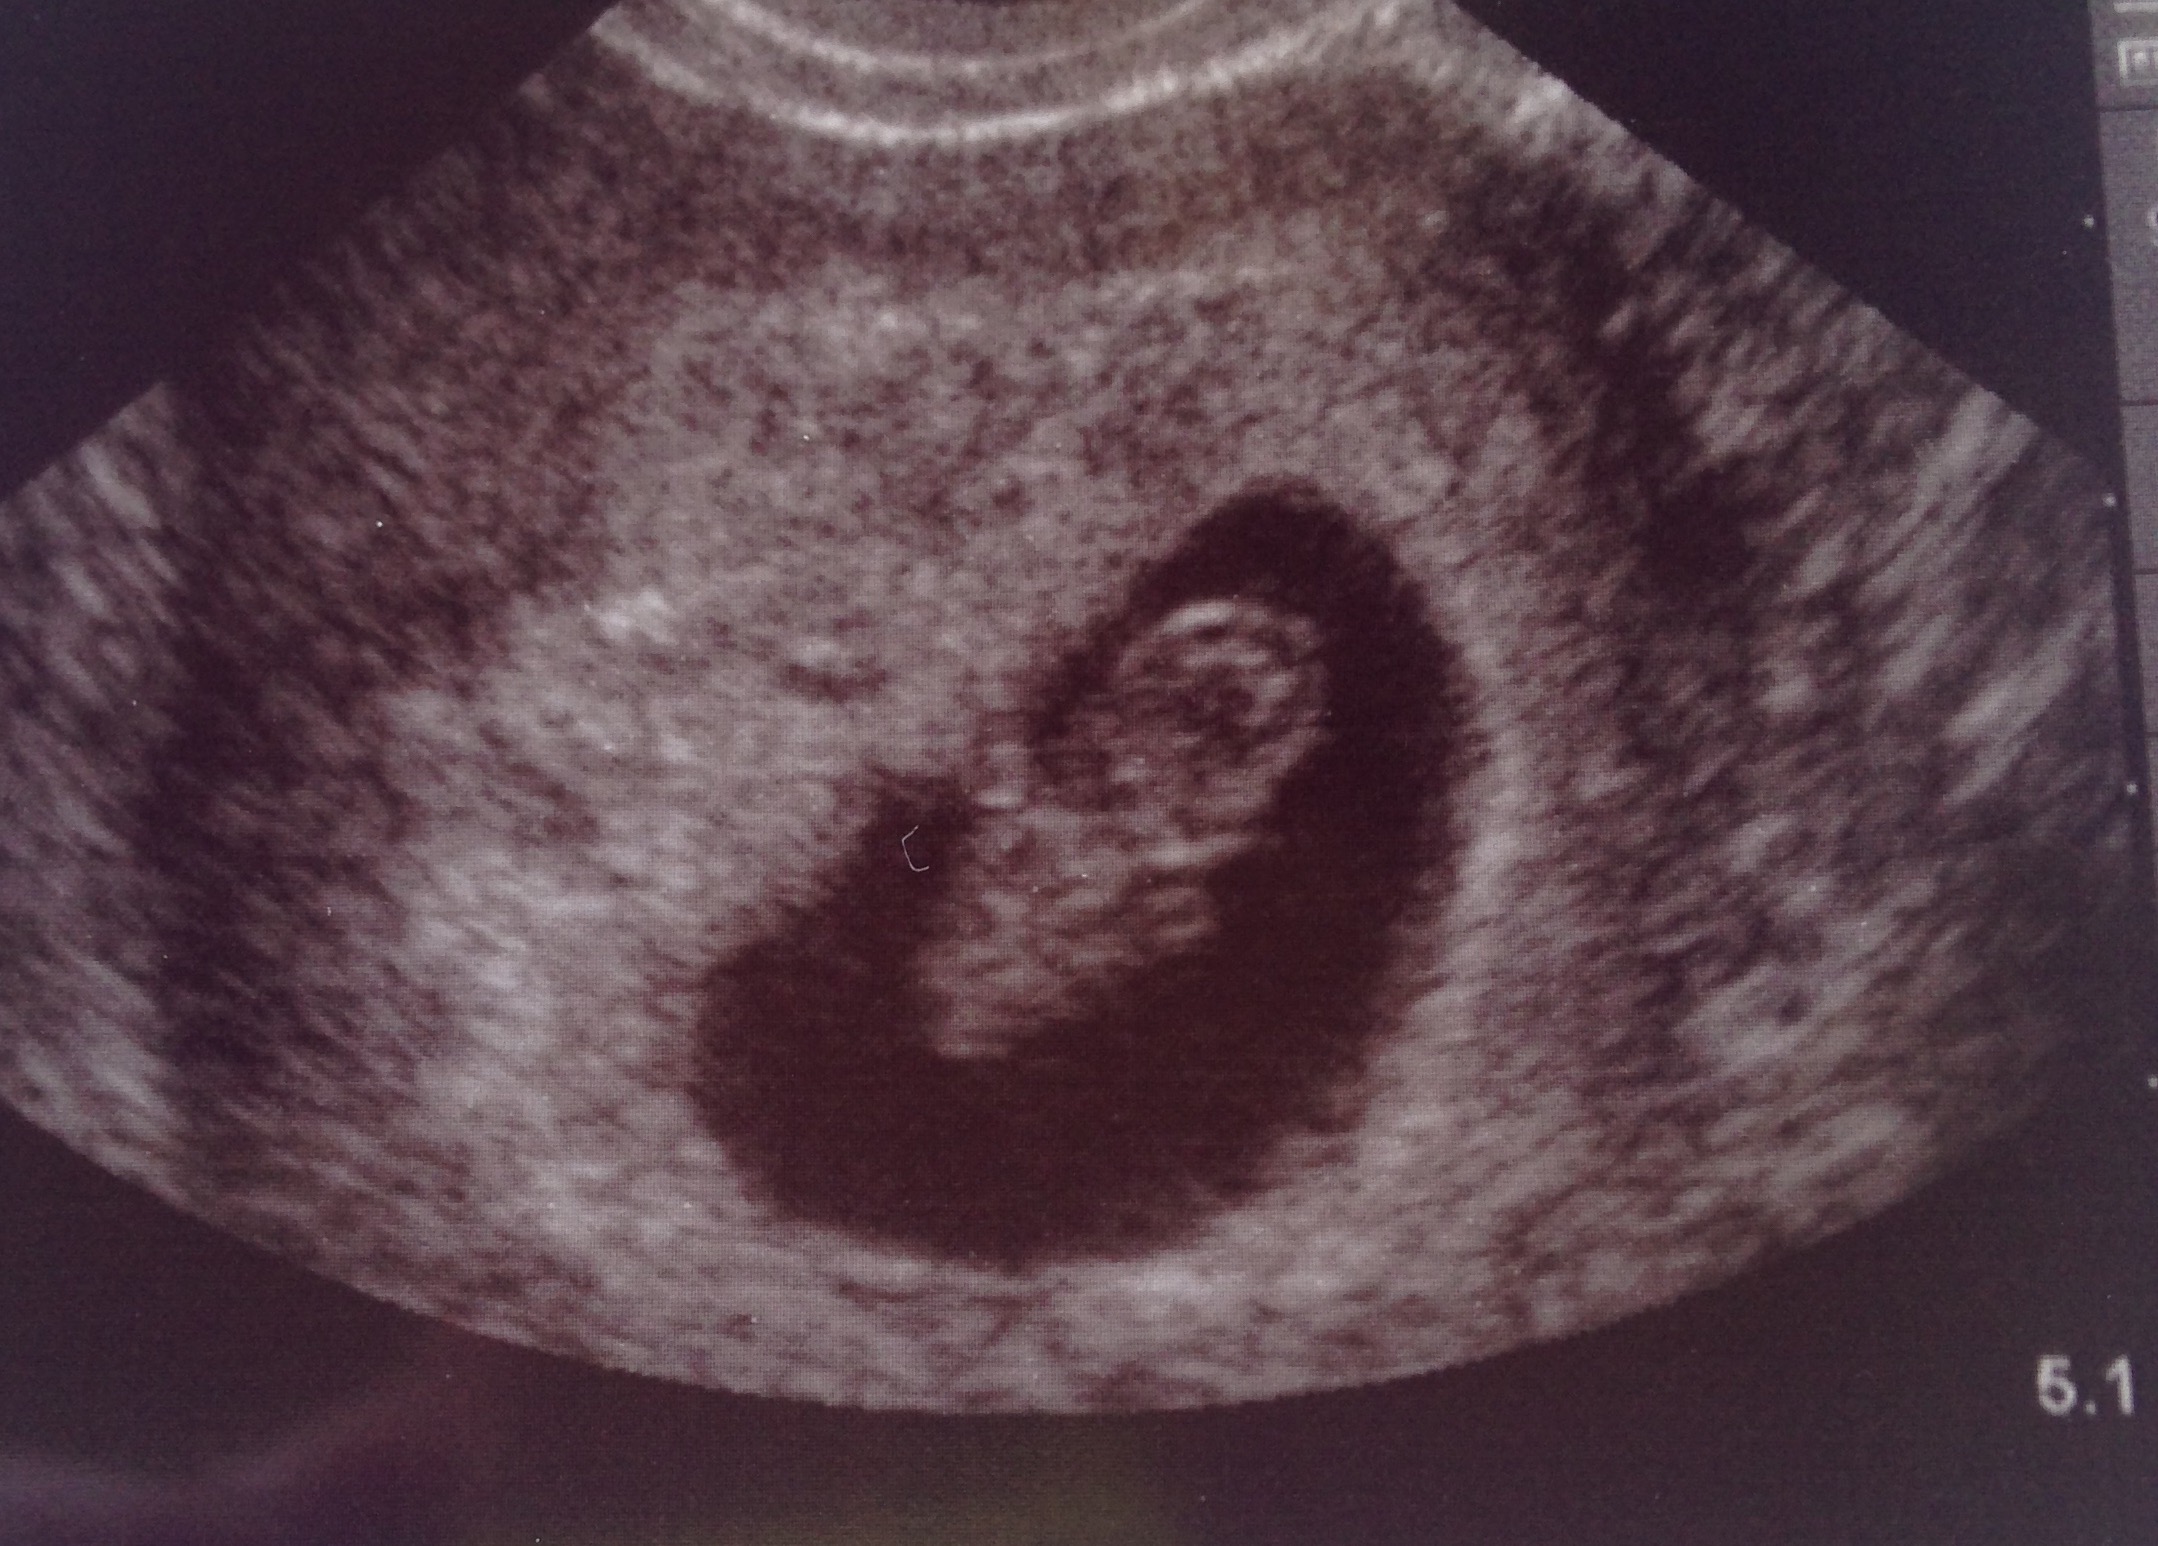

• Our little gummy bear today at 9w2d with a heart rate of 172 :)